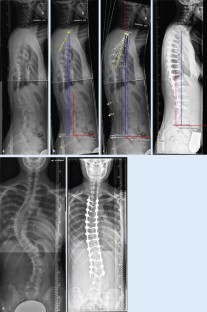

Abb. 2